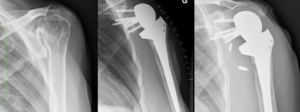

Chronic Locked Glenohumeral Joint Dislocation

Chronic locked glenohumeral dislocation can also be treated with reverse shoulder arthroplasty (Figure).[91]

Locked dislocation of a right shoulder. On the right, postoperative X-ray.